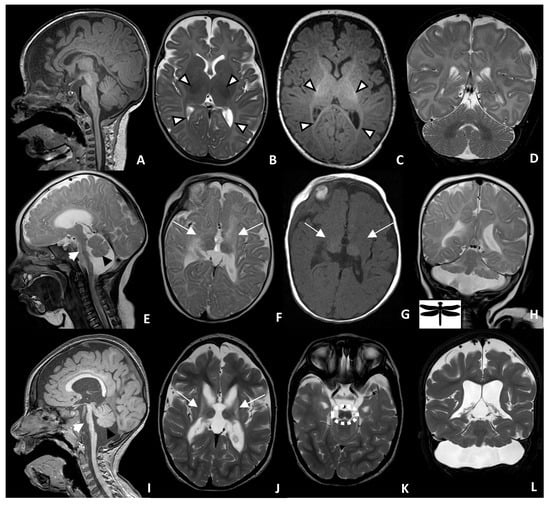

2.2. Neuroradiological Findings